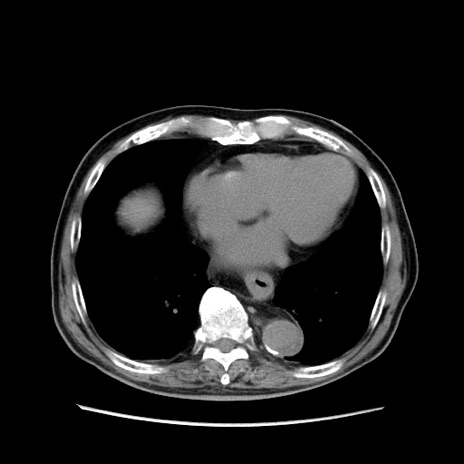

症例24(横断像)

【症例】80歳代男性

【主訴】左側腹部痛、嘔吐

【現病歴】本日早朝より左腹部に痛みあり。昼頃嘔吐認めたため、救急要請。

【既往歴】直腸癌(Mile手術)、胆摘

【身体所見】意識清明、BT 35.9℃、BP 221/93mmHg、SpO2 97%(RA) 、腹部:左ストーマ周囲に限局性の腹部膨隆あり。 膨隆部自発痛・圧痛あり・軟。

【データ】WBC 7700、CRP 0.09